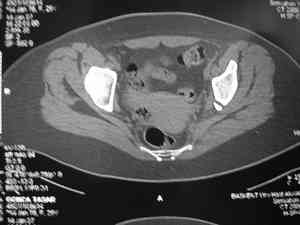

Это наблюдение 5-летней давности тогда кровопотеря составила 2,5 литра. В настоящий момент мы теряем не более 0,7-1,5 литров при одностороннем повреждении и около 2,5-3 литров тогда, когда речь идет о двусторонних повреждениях. Клинический пример.

прилагаю пример с такой же давностью травмы, репонировали аппаратом